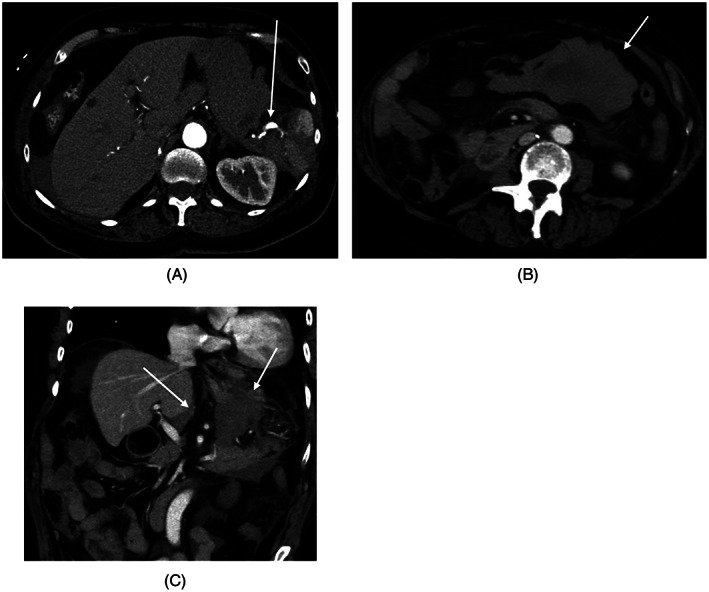

FIGURE 2.

CT SCAN with contrast acquired March, 2020 to investigate patient's left upper quadrant pain: (A) Axial CT SCAN shows ruptured splenic artery aneurysm (arrow) with perisplenic hematoma and hemoperitoneum; (B) Axial CT SCAN shows hemoperitoneum in the lesser sac (arrow) due to ruptured splenic artery aneurysm; (C) Coronal CT SCAN shows hemoperitoneum in the lesser sac (arrow) due to ruptured splenic artery aneurysm

On March 5, 2021 at 10 pm, the patient suddenly developed excruciating, sharp left upper quadrant pain that radiated to her entire abdomen. She had associated nausea and loose bowel movements but no vomiting, fever, lightheadedness, rashes or petechiae. She activated emergency medical services and was brought to her local emergency department in Northern Ontario. Her pain improved with IV opioid analgesics, but her abdomen became continually distended and her hemoglobin dropped into the low 70s. A CT of her abdomen and pelvis was performed to reveal free fluid within the peritoneal cavity and contrast pooling noted adjacent the splenic hilum, related to the splenic artery (Figure 2). The splenic artery measured 1.5 cm representing either a ruptured aneurysm or pseudoaneurysm. The patient ultimately received Vitamin K, 6 units of red blood cells and was transferred to a tertiary center elsewhere in Ontario for definitive treatment of her ruptured splenic artery aneurysm.